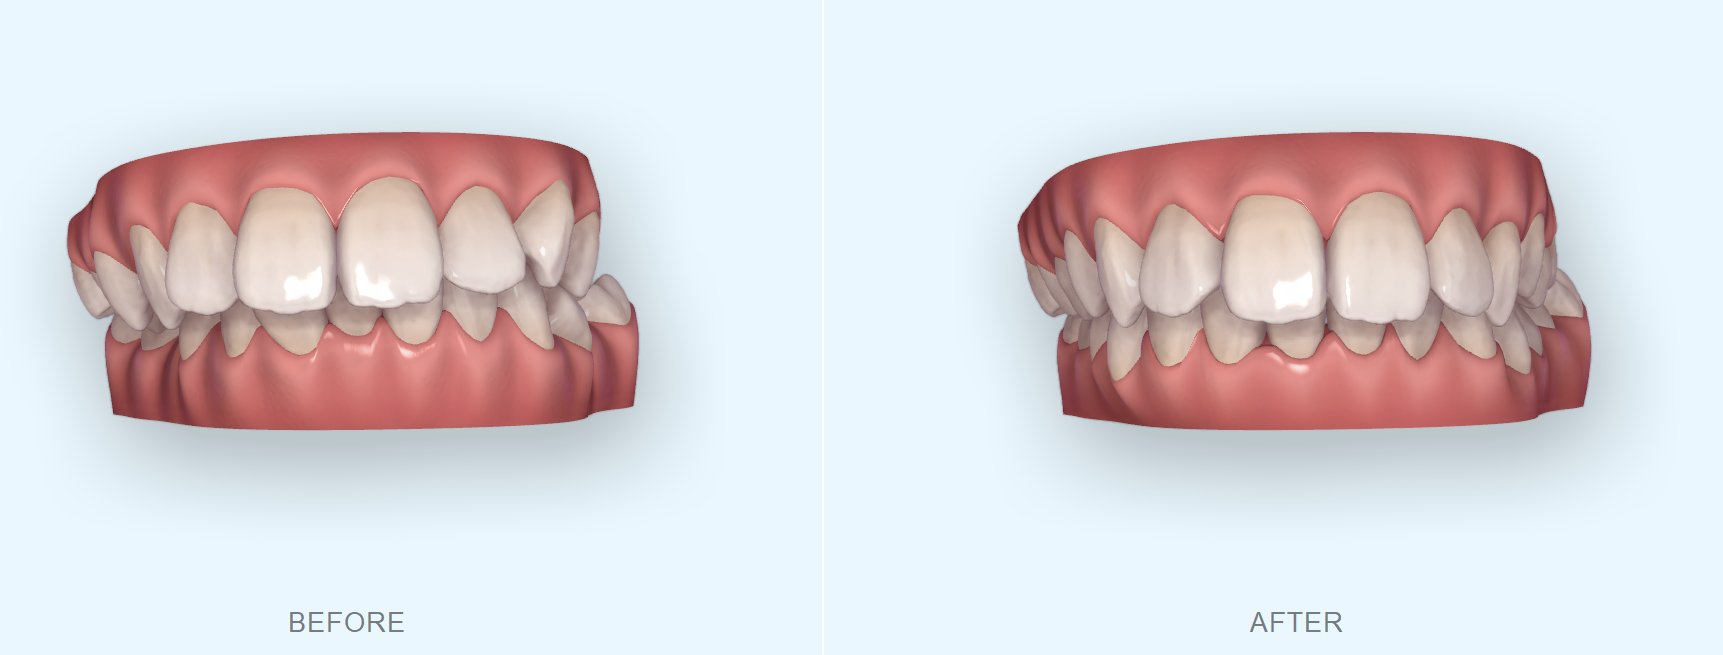

| 主訴 | 前歯のがたつきと出っ歯が気になる |

初診時の画像

確かにお顔を拝見すると、上の歯も下の歯もやや出ている感じがしますね。このような場合の治療法としては基本的には真ん中の歯の抜歯を行い、そのスペースを使用して、前歯をひっこめるのが定石です。もしくは少しずつ奥歯を後ろに移動し、さらに少し歯を削ることでスペースを作り前歯を後ろに引くのも一つです。大きく前歯をひっこめる場合にはやはり抜歯が妥当です。もう一つのご質問のマウスピース矯正で治療が可能かという質問ですが、それは可能です。しかし抜歯を行う場合には、マウスピース矯正だけでなくワイヤー矯正も併用する可能性があります。

下の前歯の叢生(がたつき)と出っ歯が気になるを主訴に来院された方の矯正相談についてのお話でした。マウスピース矯正で抜歯は難しいと言われた方もいると思いますが、近年ではマウスピース矯正も進化してきており一概に抜歯が対象外というわけではなくなってきています。実際に適応なのかどうかは矯正を行う歯科医に一度相談してみることをお勧めいたします。